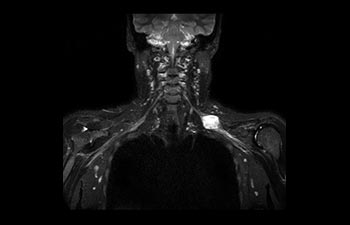

Find the right clinical applications for your needs